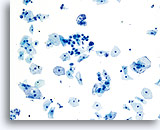

在传统的巴氏涂片上,细小的异常细胞通常会与 HSIL 相伴出现;这些细胞通常会被包裹在粘液中,或“隐藏”在背景物质内的细胞团内。由于在采用 ThinPrep 系统时,粘液和细胞碎片会经过分散处理,因此由该系统处理的标本会看起来有所不同。在使用倍镜读片时,细小的 HSIL 细胞会以单个细胞或以小细胞团的形式,在细胞的沉积背景中“凸显”出来。这些细胞应能提醒您:应更加密切地关注所呈现出的细胞物质,并查找是否有更多可供诊断的高度上皮细胞团。只要在低倍镜下看到这些细小的单个细胞或细胞团,就可在高倍镜下对这一部分玻片进行“筛查”。ThinPrep 系统的分散处理流程不会使真正的上皮细胞团发生破碎(因为高度病变存在异型性),并将会呈现出更多的单个细胞,注意到这点是至关重要的;这些是寻找病变细胞的“线索”。

对于 ThinPrep® 涂片检测,HSIL 的诊断标准如下: 单个细胞(HSIL 最重要的标准)是不对称三维胞核结构异型的表现。为掌握 HSIL 诊断,必须对此概念有明确的理解。不良胞核的结构将发生异型变化;对于这些胞核而言,只有对单个细胞的焦距进行上下控制,才可对这些胞核做出彻底的诊断。此概念是最难以在书本图片(二维页面)上展示的;然而,这却是最为重要的。

试想想对一个微缩的花椰菜、握紧的拳头、棒球或扁桃腺的焦距进行上下对焦。葡萄干的表面看起来像什么?正常胞核的形状相对较圆或呈椭圆形,并且其表面也是平滑的。不良细胞将具有凸起、凹陷、褶皱、裂纹和奇怪的隆起。这些非常明显的异型性是异生性(特别是 HSIL)的基本特征;而由于传统的细胞涂片在固定和染色过程中会存在各种干扰物质,上述的细节往往会在传统的细胞涂片丢失 , 这样令传统涂片的诊断能力造成限制。

这些三维细胞结构的异型性可与简单的“不规则细胞核轮廓”区别开来;在 ThinPrep® 玻片上,这些将是良性细胞的一种特征表现。由于是二维的, 由于是二维的,当检查员在显微镜下上下对焦时,这些“褶皱”像裂缝或山脉般难以在胞核中心被追踪,这样会为无经验者做成相类似的假像。

在玻片上,并不是每个不良细胞都会呈现出这些三维结构的异型性;但是,在这些玻片上,这些异型性至少会在一些细胞中较为明显。显然,染色质量直接关系到是否能够看到胞核“内部”。(与传统的巴氏涂片相比,所有的 ThinPrep® 涂片检测都使得细胞变化更为明显;但如果对反应物进行过度染色,或有轻微腐败,都将对这种最为重要的评估标准造成直接影响)。此外,与细胞凹陷或简单的褶皱(会达到胞核的全部宽度,具有“相似本体”,并会造成一定的难度)相比,这些三维结构的缺陷应该是不对称的。由于这些胞核的三维异型性能够得到放大,因此能够为 HSIL 诊断提供依据。